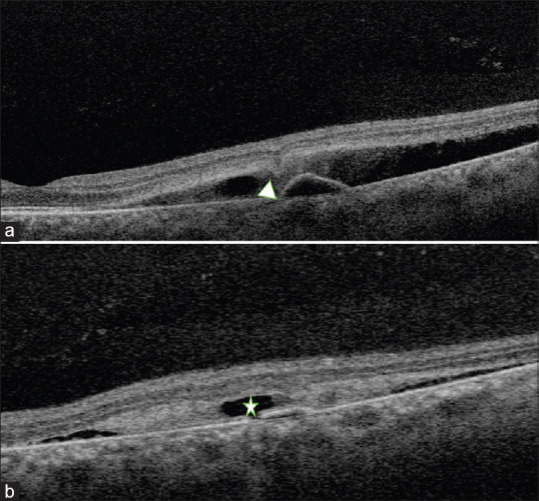

Fluorescein-free detection of focal leak in a patient with acute central serous chorioretinopathy.

Fundus fluorescein angiography (FFA) is considered the gold standard for identifying focal leaks in central serous chorioretinopathy (CSCR). However, there are situations where FFA cannot be performed, and alternative noninvasive investigations are required to pinpoint area of focal leaks. We present a case of a 36-year-old female patient with bilateral steroid induced acute CSCR with three distinct fluorescein-free signs converging in the same area indicating presence of focal leak.